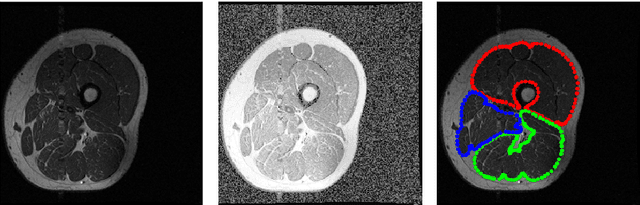

Abstract:Image segmentation is a complex mathematical problem, especially for images that contain intensity inhomogeneity and tightly packed objects with missing boundaries in between. For instance, Magnetic Resonance (MR) muscle images often contain both of these issues, making muscle segmentation especially difficult. In this paper we propose a novel intensity correction and a semi-automatic active contour based segmentation approach. The approach uses a geometric flow that incorporates a reproducing kernel Hilbert space (RKHS) edge detector and a geodesic distance penalty term from a set of markers and anti-markers. We test the proposed scheme on MR muscle segmentation and compare with some state of the art methods. To help deal with the intensity inhomogeneity in this particular kind of image, a new approach to estimate the bias field using a fat fraction image, called Prior Bias-Corrected Fuzzy C-means (PBCFCM), is introduced. Numerical experiments show that the proposed scheme leads to significantly better results than compared ones. The average dice values of the proposed method are 92.5%, 85.3%, 85.3% for quadriceps, hamstrings and other muscle groups while other approaches are at least 10% worse.

Abstract:Image segmentation is a crucial but challenging task that has many applications. In medical imaging for instance, intensity inhomogeneity and noise are common. In thigh muscle images, different muscles are closed packed together and there are often no clear boundaries between them. Intensity based segmentation models cannot separate one muscle from another. To solve such problems, in this work we present a segmentation model with adaptive spatial priors from joint registration. This model combines segmentation and registration in a unified framework to leverage their positive mutual influence. The segmentation is based on a modified Gaussian mixture model (GMM), which integrates intensity inhomogeneity and spacial smoothness. The registration plays the role of providing a shape prior. We adopt a modified sum of squared difference (SSD) fidelity term and Tikhonov regularity term for registration, and also utilize Gaussian pyramid and parametric method for robustness. The connection between segmentation and registration is guaranteed by the cross entropy metric that aims to make the segmentation map (from segmentation) and deformed atlas (from registration) as similar as possible. This joint framework is implemented within a constraint optimization framework, which leads to an efficient algorithm. We evaluate our proposed model on synthetic and thigh muscle MR images. Numerical results show the improvement as compared to segmentation and registration performed separately and other joint models.